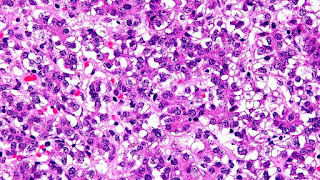

Hepatoblastoma is an uncommon malignant liver cancer occurring in infants and children and composed of tissue resembling fetal liver cells, mature liver cells, or bile duct cells. They usually present with an abdominal mass. The disease is most commonly diagnosed during a child's first three years of life. Alpha-fetoprotein (AFP) levels are commonly elevated, but when AFP is not elevated at diagnosis the prognosis is poor.

Hepatoblastomas originate from immature liver precursor cells, are typically unifocal, affect the right lobe of the liver more often than the left lobe, and can metastasize. They are categorized into two types: "Epithelial Type" and "Mixed Epithelial / Mesenchymal Type."